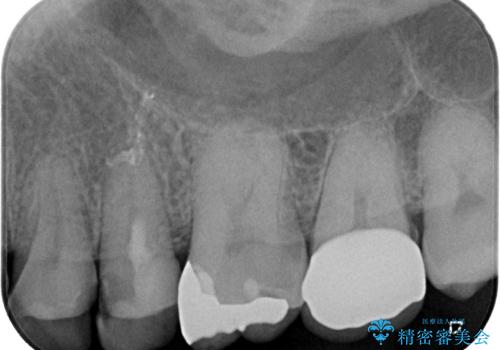

- 歯の間に物が詰まるとのことで来院された患者様です。以前に歯冠部の神経の一部を取り除き、MTAセメントという特殊なセメントを充填し、歯根部の神経を温存する生活歯髄療法(VPT)を行われておりセラミックの詰め物にて修復されていました。セラミックの詰め物が少し欠けたことにより食べ物が挟まってしまう状況でした。

まず神経の生活反応を確認し、今回はセラミックの詰め物のやり替えではなく、セラミックのかぶせ物で治療を行っていくこととしました。